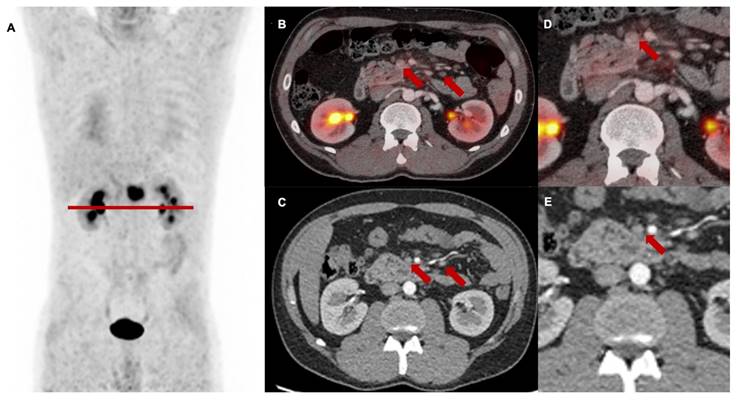

Figure 4

[68Ga]Ga-FAPI-46 PET/CT of a patient with locally recurrent pancreatic adenocarcinoma before (Baseline, A-C) and 3 months after (first follow-up D-F) treatment with chemoradiotherapy (Patient #7). A and D maximum intensity projections, B and E transaxial fusion of PET/CT of the upper abdomen, C and F transaxial contrast-enhanced CT scan of the upper abdomen. Red arrows (A-C) mark intense FAPI uptake of small-volume tumor tissue at the minor gastric margin. The red arrow in F marks stable tumor tissue without measurable FAPI signaling post-treatment. SUVmax at 1st follow-up was 8,2 / SUVmean was 5,0 and at 2nd follow-up 1,7 / 1,4, respectively. In the absence of the detection of vital tumor remnants in the [68Ga]Ga-FAPI-46 PET/CT, complete remission of the disease was assumed. In this case, the significant decrease of the FAPI uptake in the 1st follow-up scan was associated with local tumor control within the next 6 months after therapy. Patient #7 showed local progression in the 3rd follow-up scan 9 months post CRT.

T staging at follow-up

Local tumor control (i.e., stable disease or remission) after high dose chemoradiotherapy was achieved in 5 of 13 patients (38%) with mostly concordant T classification or minor variations. Here, reduced FAPI expression correlated with either reduced tumor volume or no measurable lesion (example shown in Figure 4).